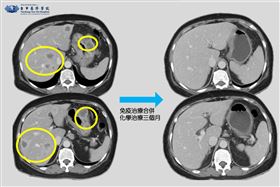

晚期胃癌免疫治療合併化療!一成腫瘤消失

六十六歲無特別病史的徐女士因上腹痛解血便、呼吸急促前...

解黑便2個月罹胰臟癌4期 7個月病情逆轉

台中一名67歲婦人,因解黑便就醫治療2個月沒有改善,...